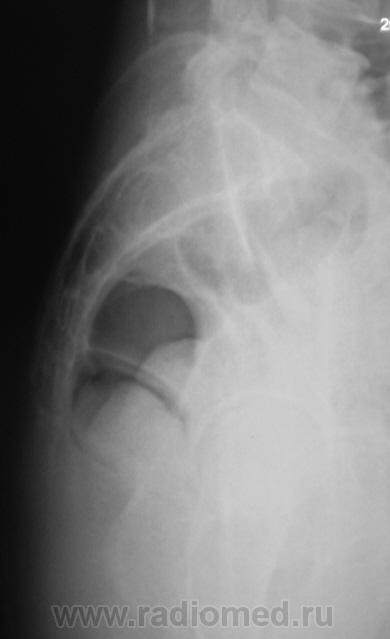

Из анамнеза известно, что примерно 2 месяца тому "летела" со сноутборга около 200 метров. Сейчас беспокоят боли в области спины, крестца и лонного сочленения. УЗИ было сделано всего, что только можно, везде - "норма". Хирурги, вроде-бы тоже ничего не находят. Но боли, видать значительные, походка вынужденная. На рентгенографию была направлена, как жест отчаяния, мол может быть, что-то найдут.

Рентгенограмма в прямой проекции.

1. Не исключаю поперечный перелом S5.

2. Лонное сочленение очевидно,подверглось значительному растяжению (имеется локальный вакуум-феномен слева), умеренно выраженые явления симфизита (опять же - постравматического).

Посттравматический симфизит - это такой медицинский диагноз есть? Тогда уж лучше - симфизопатияУлыбаюсь.  По поперечному перелому Л5 - тангенциальный эффект, сложение теней. По хорошему, надо бы доснять поясничный отдел позвоночника, в том числе в косых проекциях - на дугоотростчатые суставы, и грудо-поясничный переход.

1. По первым снимкам не отпускало впечатление о повреждении левого крестцово-подвздошного сочленения. После подготовки вроде-бы все нормально, но все равно что-то гложет.

2. А на боковой массе крестца справа разве не линия консолидирующегося перелома?

Верятность перелома остистого отростка Л4 очень велика. Это находит подтвеждение и на боковом снимке.